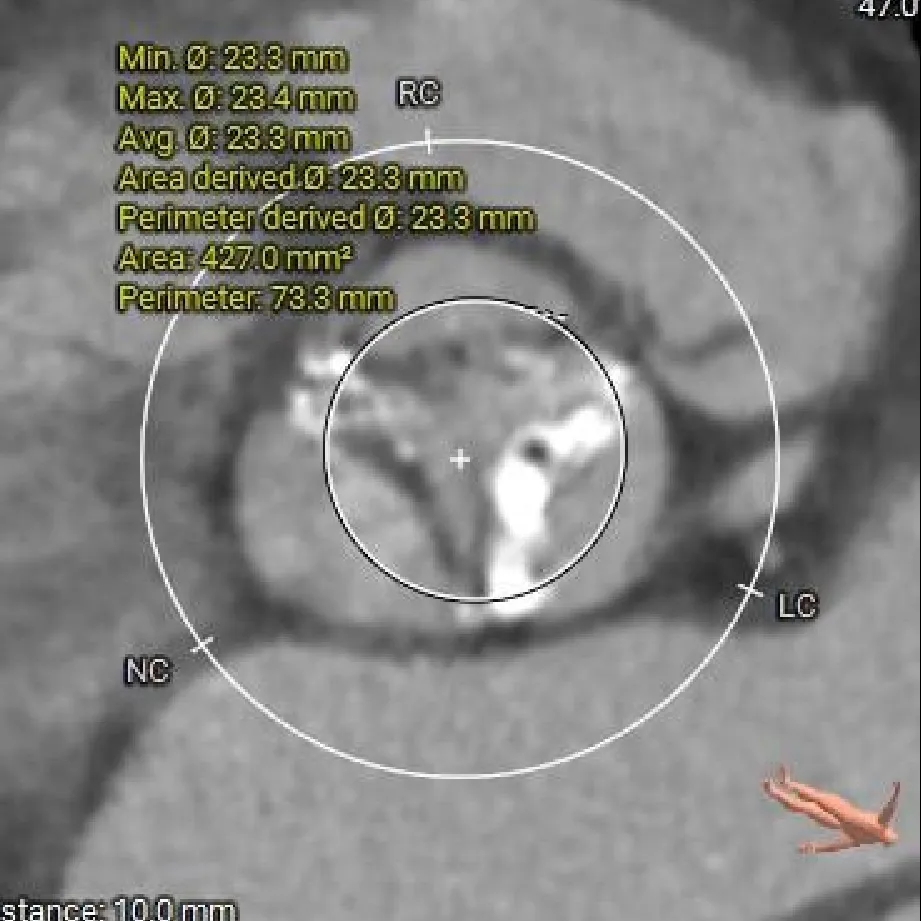

瓣上 10mm

23.3mm